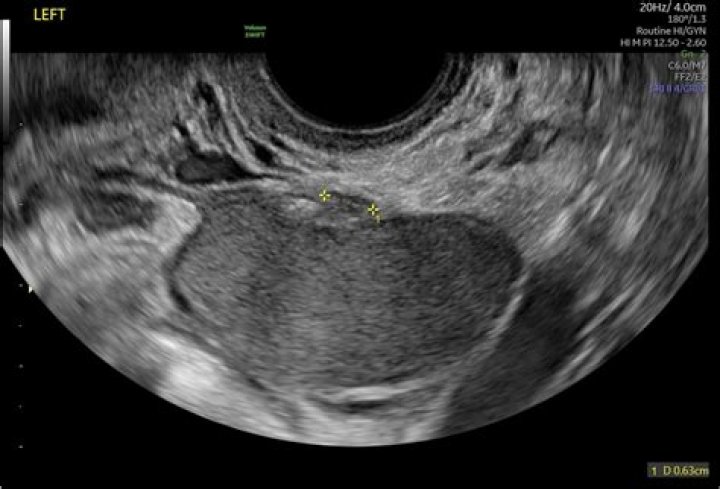

Read JournalWe have shown that identifying the subserosal hypoechoic rim and endomyometrial junction indistinctness on ultrasound scans can reliably help to distingui...